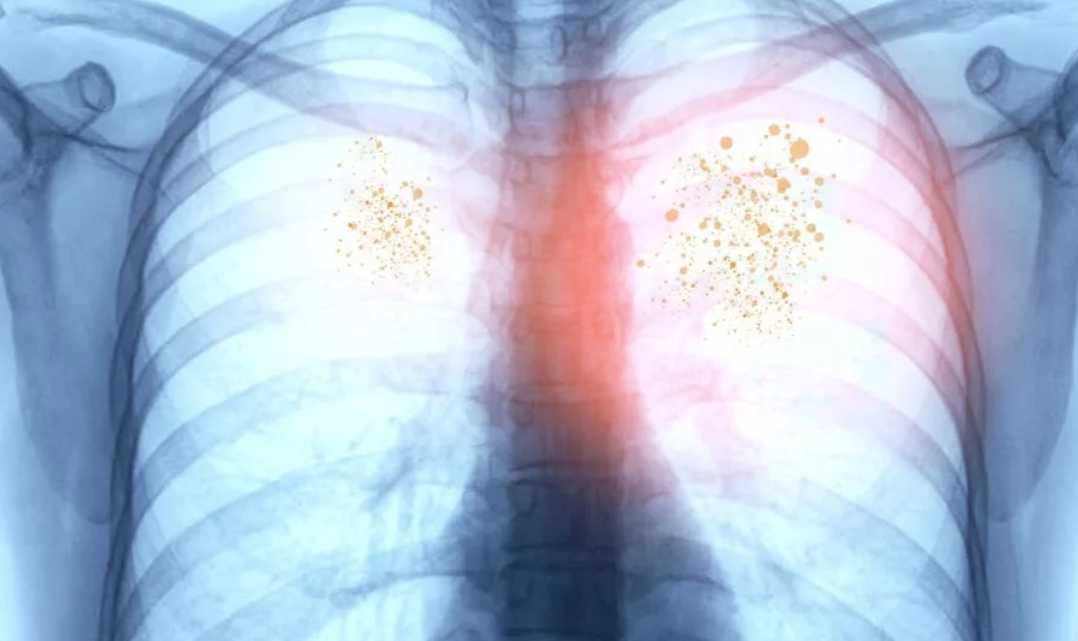

Некоторые типы пневмонии приводят к суставным, головным болям, образованию красных пятен на лице, шее. При обследовании врач замечает хрипы в легких. В этом случае нужна дополнительная диагностика — рентген, КТ.

Чтобы точно убедиться в наличии пневмонии без температуры, поставить точный диагноз, специалист выслушивает жалобы пациента, осматривает грудную клетку, проверяет симметричность дыхания. Прослушивание легких позволяет выявить хрипы, а больные участки во время простукивания издают приглушенный звук.

Еще требуется анализ крови, мочи и мокроты. Рентген поможет выявить очаг воспаления в легких, его масштабы. Если есть подозрения на этот недуг, нужно сразу же обратиться к врачу. Самостоятельно поставить себе диагноз не получится. В больнице проводится полное обследование, что поможет точно определить вид заболевания.